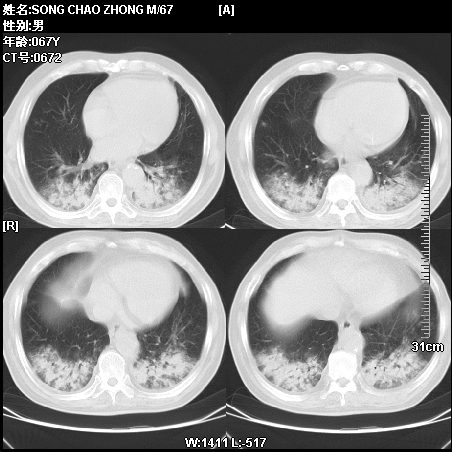

肿瘤科住院病人,都有食管癌史,都有放化疗治疗,两下肺病变是转移灶?还是其他原因造成?请老师指点

病例二 食管癌4个月,咳嗽咳痰,呼吸困难

第一个病例我感觉不是转移,第二个是个放射性肺炎;但两个都有纵隔淋巴结肿大,以第二个为主;请楼主参考